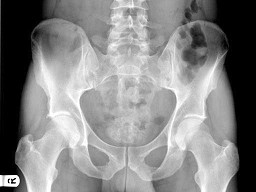

男,根据其正常骨盆影像图像,判断其最可能的年龄()

题型: 单选题 分类: 放射医学

• A.68岁左右

• B.58岁左右

• C.18岁左右

• D.48岁左右

• E.28岁左右